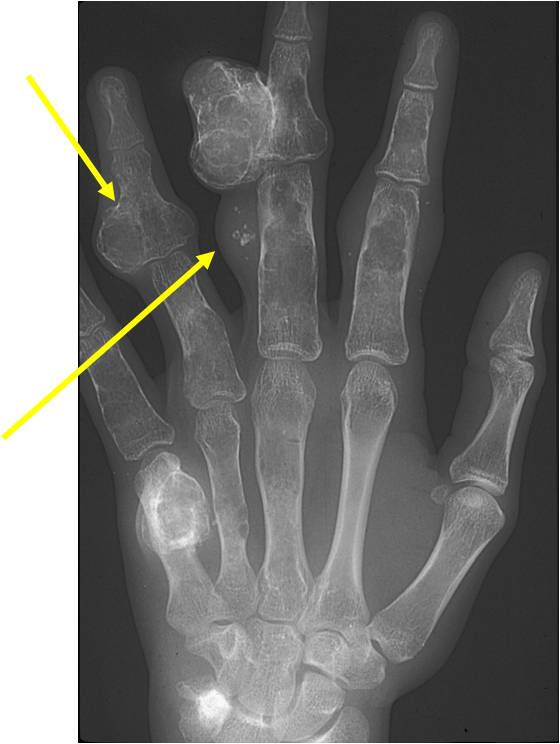

- May be predominantly unilateral or affect a single extremity/limb

- Affected limb is often shortened and deformed and angulated

Enchondromas in enchondromatosis may involve the metaphysis, diaphysis, epiphysis and articular cartilage